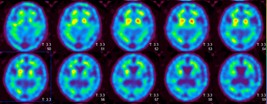

123I ]β-CIT シンチグラム (通称 DATシンチ)

PD 線条体(特に後部)の取り込み(C I T値)低下

正常 線条体の取り込みは保たれている